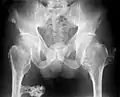

The diagnosis of HMO is based upon establishing an accurate correlation between the above-mentioned clinical features and the characteristic radiographic features. Family history can provide an important clue to the diagnosis. This is supplemented by testing for the two genes in which pathogenic variants are known to cause HMO namely EXT1 and EXT2. A combination of sequence analysis and deletion analysis of the entire coding regions of both EXT1 and EXT2 detects pathogenic variants in 70–95% of affected individuals.[3][4] The hallmark of radiographic diagnosis is the presence of osteochondromas at the metaphyseal ends of long bones in which the cortex and medulla of the osteochondroma represent a continuous extension of the host bone. This is readily demonstrable in radiographs of the knees.[3][1]

Multiple osteochondromas causing deformity of the forearm (shortening of the Radius with secondary bowing of the Ulna).

multiple osteochondromas at the pelvis